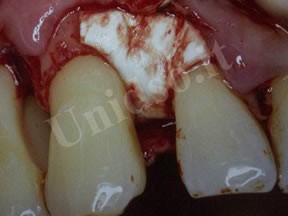

L’ Unità Operativa di Parodontologia e Igiene Orale si compone di 5 sezioni. L’attività’ clinico-assistenziale è svolta da diversi odontoiatri, supportata da igienisti dentali e assistenti alla poltrona, ed è articolata sulla base di appuntamenti programmati. Nell’Unità Operativa di Paradontologia e Igiene Orale del DSMOB si eseguono le seguenti prestazioni odontoiatriche: istruzioni d’igiene orale, ablazione tartaro, full radiografico, terapia dell’alitosi, levigatura radicolare, chirurgia parodontale riparativa, resettiva e rigenerativa e chirurgia plastica dei tessuti molli parodontali.